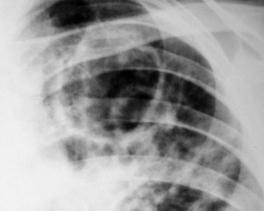

Рис.1. Очаговые тени